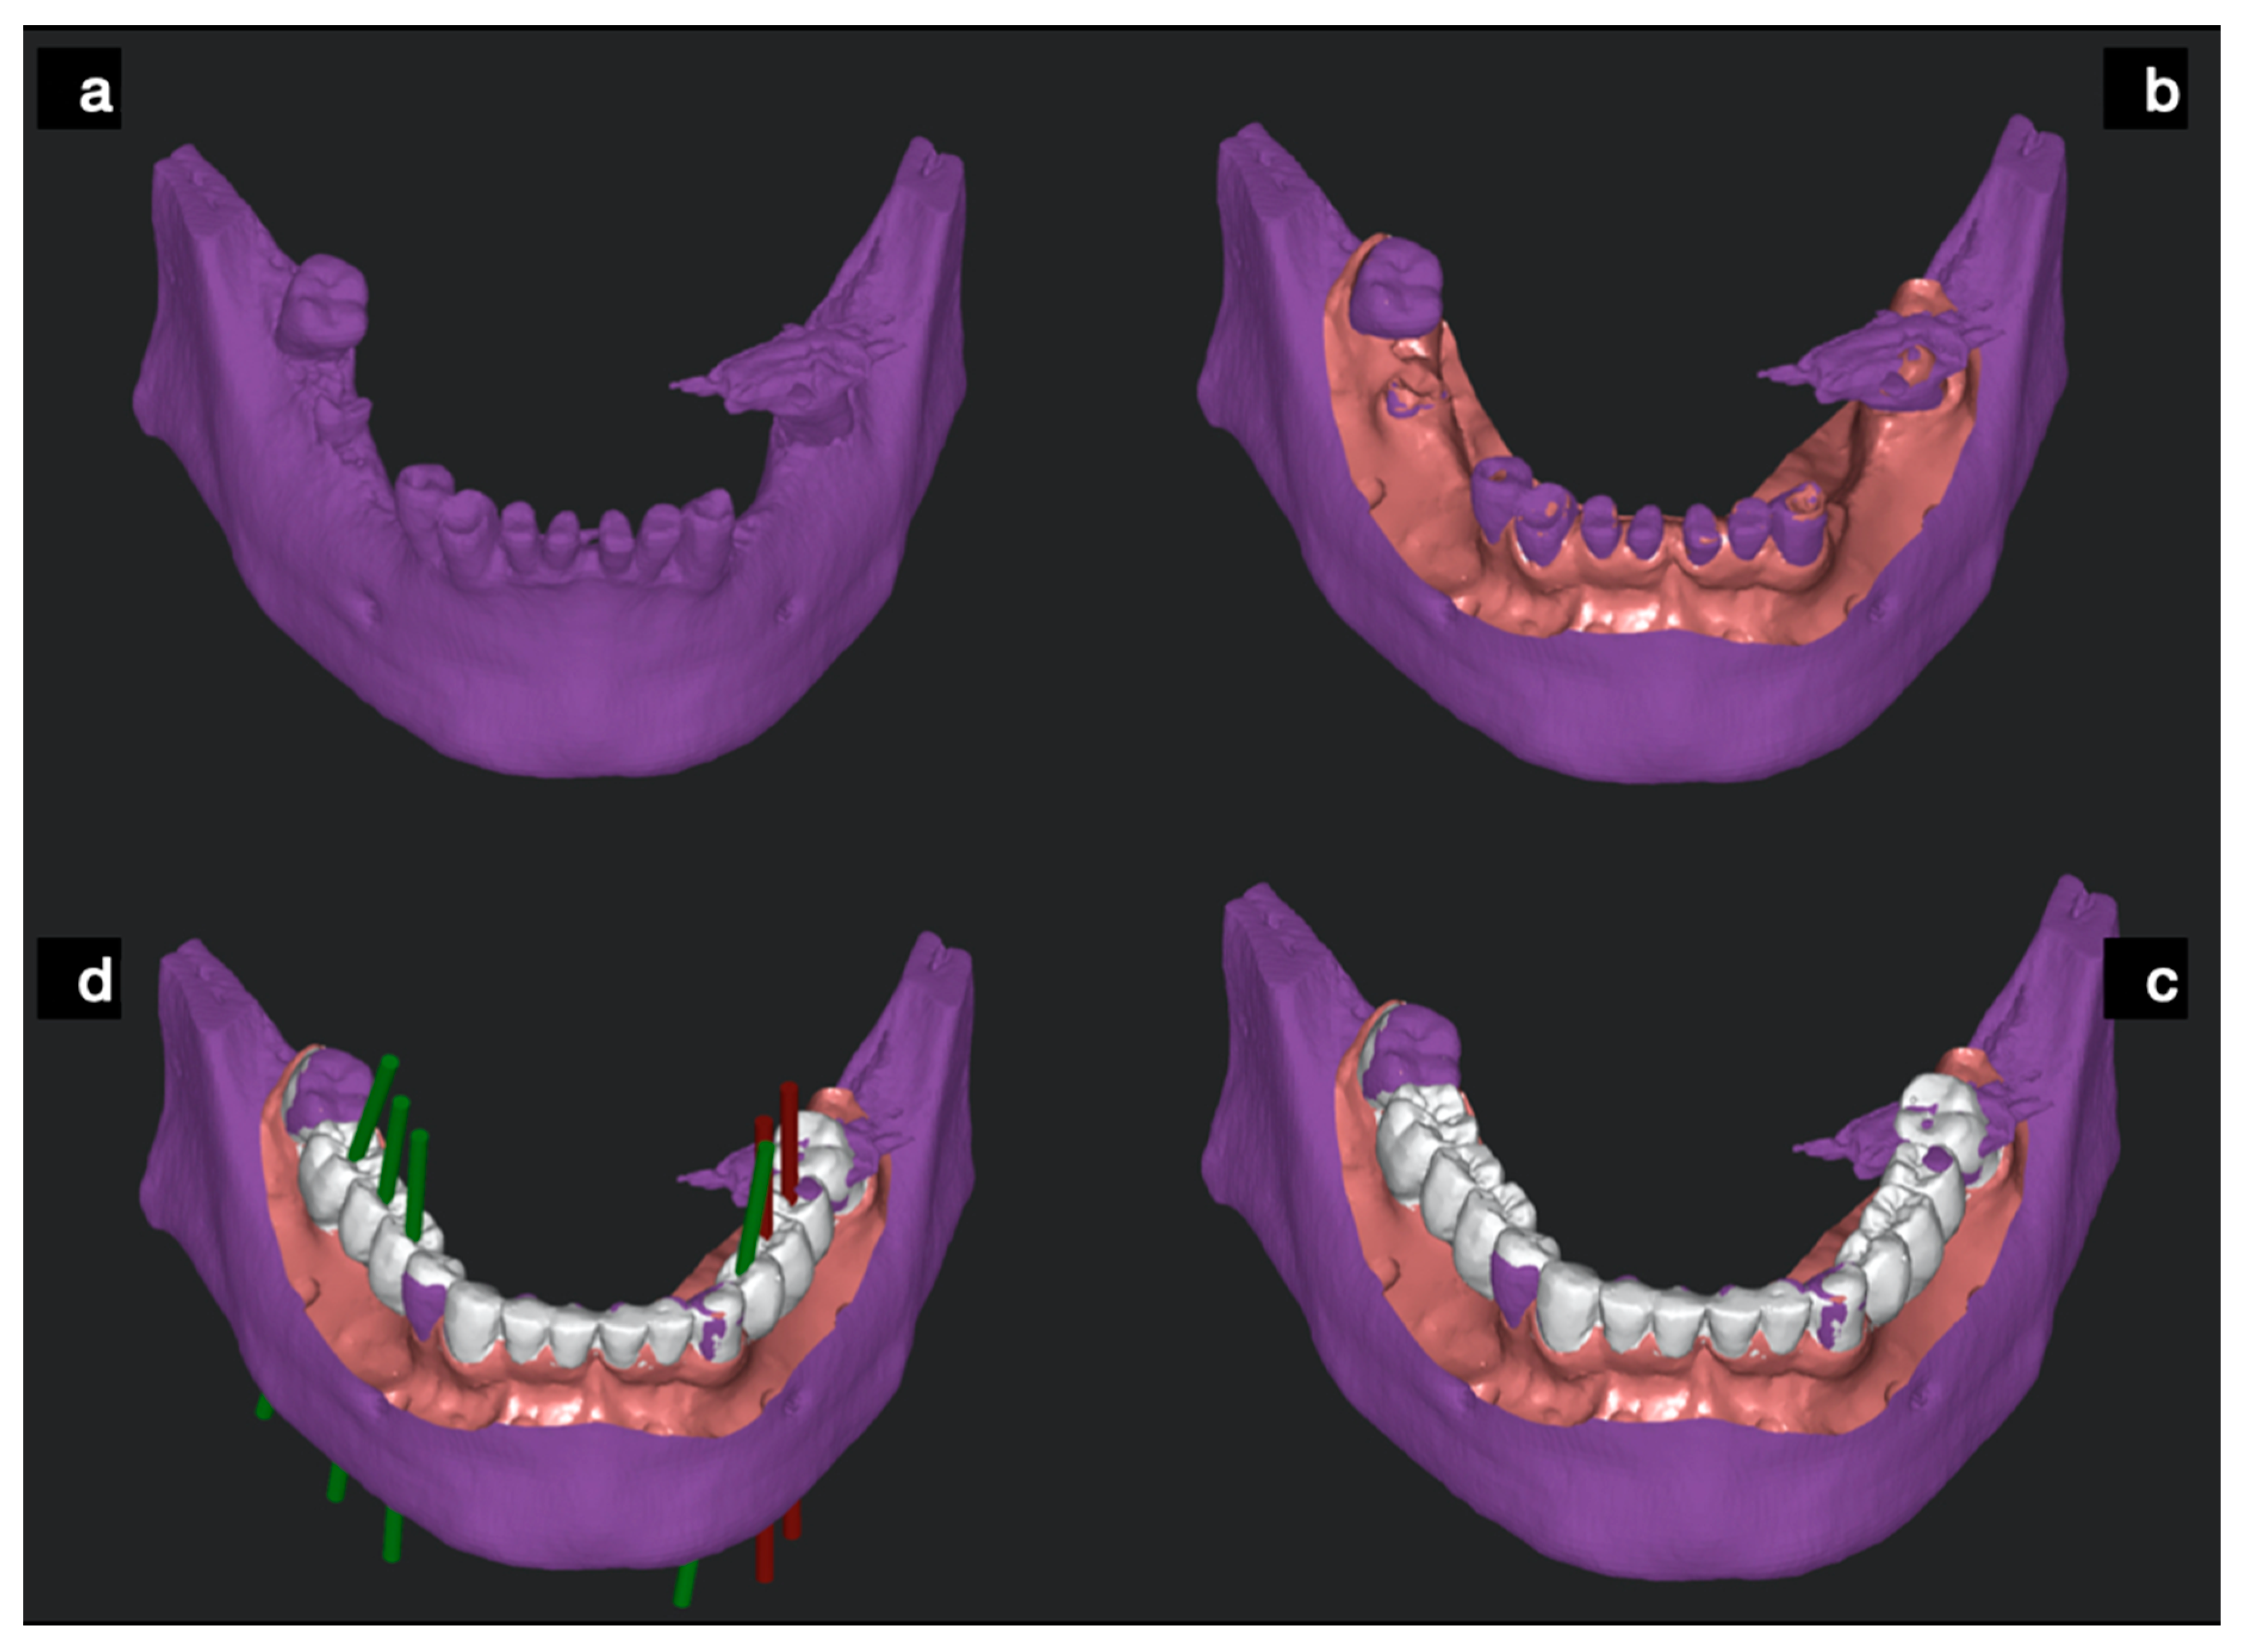

2.1. Static Computer Aided Implantology Workflow (SG)

2.2. Dynamic Computer Aided Implantology Workflow (ND)

2.2.1. Plan

2.2.2. Trace

2.2.3. Place

2.3. Free Hand Workflow (FH)